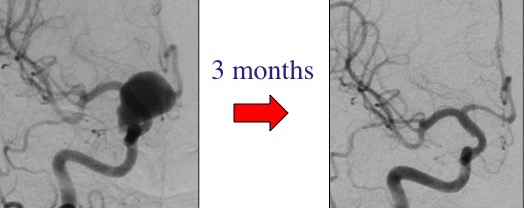

This is an example of a giant brain aneurysm that was treated with the PED flow diverter. Follow-up angiogram done in 3 months show that the aneurysm is cured completely! This aneurysm will not recur (or come back)!